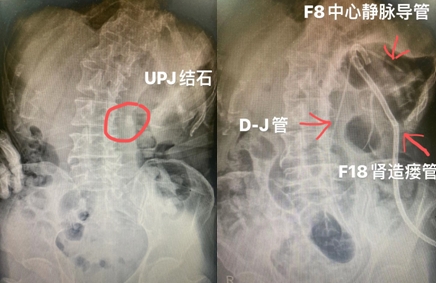

术前术后KUB对比

术前术后对比图

术后复查CT发现未损伤胸腔及肠管,穿刺通道无出血,结石无残留,一期清石率100%。复杂病例的高效治疗,标志着齐医附属二院泌尿外二病区的泌尿系结石的诊治能力已跃居省内一流水平。